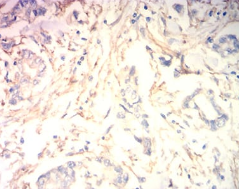

IHC    1/200 - 1/1000